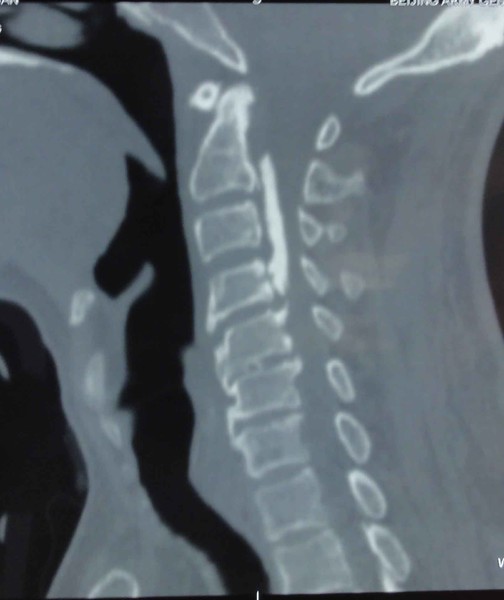

男性患者65岁,发病一年前曾因颈椎部不适在当地院就诊,颈椎CT提示后纵韧带钙化,颈椎管狭窄,如下图

图1 患者颈椎CT显示后纵韧带钙化,颈椎管严重狭窄